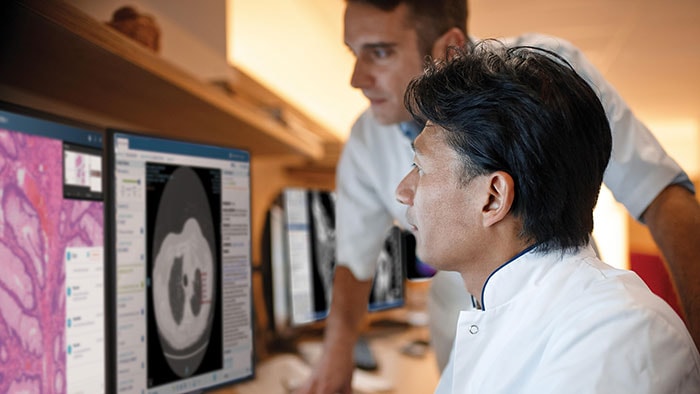

The authorization by the FDA for digital pathology in the US, the world’s largest healthcare market, constitutes a watershed moment for the healthcare industry. Pathologists work in laboratories, in clinics and on hospital wards. Digital pathology enables them to view and diagnose digital images of surgical pathology slides prepared from biopsied and resectioned tissue. It means we can leverage all the benefits that result when images are digitized, including the reporting and billing of diagnostic results.

Rather than looking directly at a tissue sample mounted on a glass slide under a conventional light microscope, the Philips IntelliSite Pathology Solution enables pathologists to read and share tissue slides digitally in order to make diagnoses. It could help make critical health information available to patients and healthcare professionals faster and at lower cost.